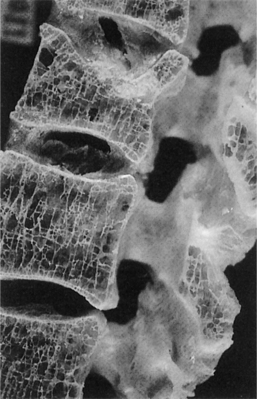

Because bone turnover is a surface event and trabecular bone has a high surface area, bones rich in trabeculae (e.g., vertebrae, metaphyseal segments of long bones, and the calcaneus) are more active, metabolically exhibiting a greater rate of turnover and resorption with loss of structural integrity during the aging process (Fig. 24-1). The ultimate strength of a specific bone appears to be related to the percentage of trabecular versus cortical bone, the structural integrity, and the trabecular interconnections of the bone.150

Osteoporosis develops when new bone formation falls behind resorption, possibly related to impaired new bone formation due to declining osteoblast function (Fig. 24-2). The onset of bone loss is likely to be genetically predetermined, and the subsequent rate of bone loss may also be influenced by genetic factors.

Figure 24-2 Osteoporosis of the lumbar vertebra with generalized loss of bone. The vertical plates have become perforated and the number of horizontal cross-braces are decreased markedly in proportion to the vertical plates. (From McPherson RA: Henry’s clinical diagnosis and management by laboratory methods, ed 21, Philadelphia, 2006, WB Saunders.)

Fractures are usually diagnosed by radiograph examination (x-ray) that demonstrates the fracture (Fig. 24-5) and also reveals the osteopenia leading to the diagnosis of osteoporosis. Once osteopenia is noted, other causes of metabolic bone disease must be ruled out, including hyperthyroidism, hyperparathyroidism, osteomalacia, testicular failure, malignancies, and so on. Diagnostic criteria for men with this condition are at present based on those for women, although the validity of this approach is under discussion.131 Histologically, a thinning of cortical bone and a reduction in the number and size of the trabeculae of cancellous bone occurs (see Fig. 24-1). Thirty percent or greater bone density loss must occur before such abnormalities can be noted on an x-ray film.